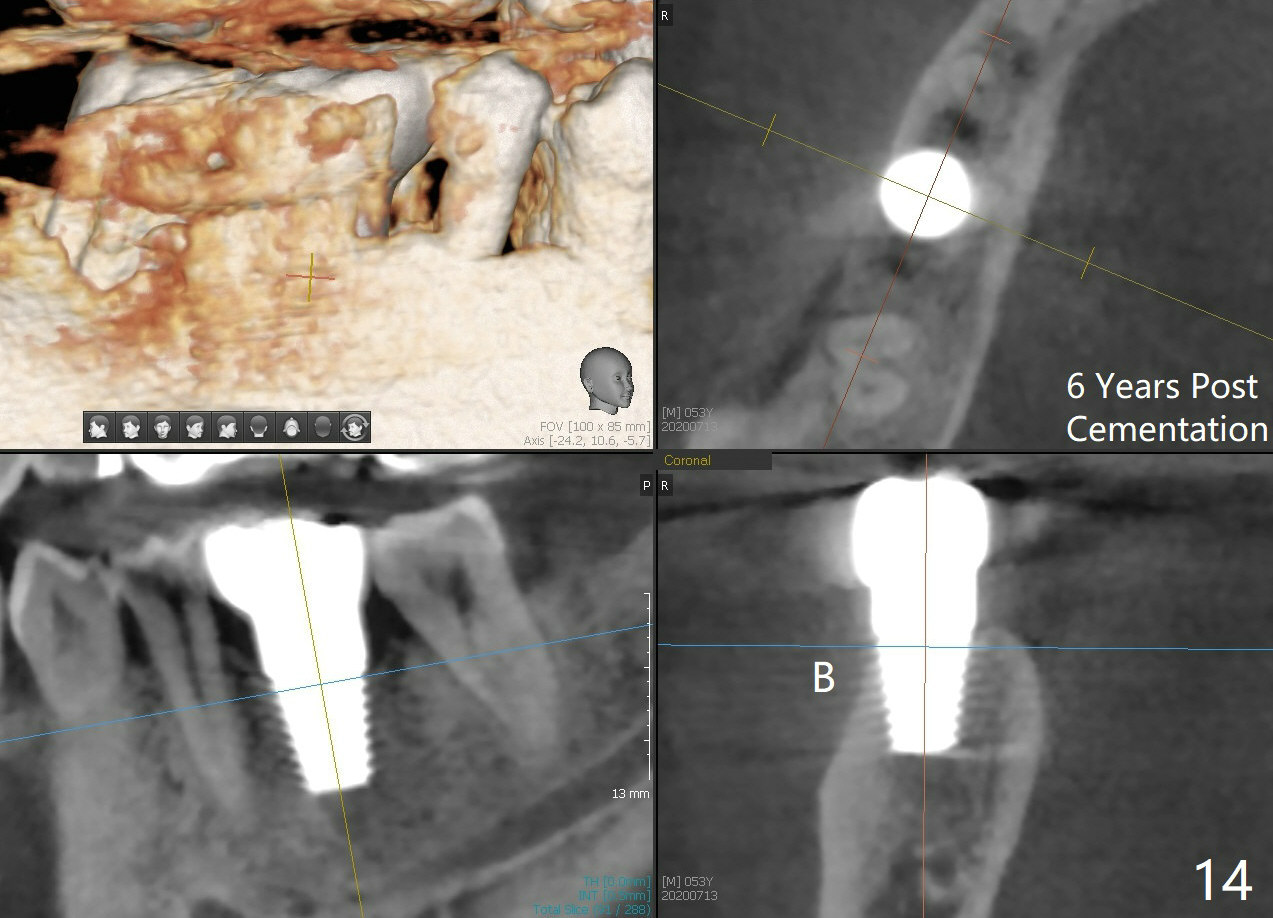

When a large implant is placed in a molar socket, one dimension of the remaining socket is small (buccolingual for lower, mesiodistal for upper). It is apparent that the mandibular buccal and lingual gingiva is relatively loose for the most time, the mesial and distal socket could be closed by suturing and perio dressing. The maxillary palatal gingiva is particularly thick and tough to be approximated. It appears necessary to develop a technique using an immediate provisional to close the socket or place an abutment. Cortex-like bone seems to have grown into the mesial thread spaces 3 years post cementation (Fig.13 <). The 7x17 mm implant was placed buccal (Fig.14 B). The slowly resorbed buccal plate seems to darken the buccal gingiva (Fig.15 B). The bone next to the implant is dense 6 years post cementation (Fig.16 *). The implant at 19 should be smaller and placed lingual.